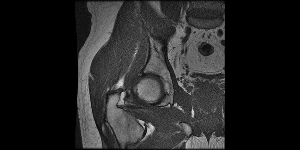

Infelizmente, devido aos impactos causados pelos chutes fortes, ele acabou desenvolvendo uma lesão grave nos quadris. O que fez com que acabasse sentindo cada vez mais dor ao treinar e dar aulas. As dores fizeram com que ele precisasse abrir mão de seu sonho. E mesmo parando com os treinos, ainda sente muita dor, o que acaba prejudicando seu trabalho, devido as posições necessárias para o serviço. E também seu dia a dia em casa, com a família e na hora de dormir porque as dores permanecem o tempo todo.

O único jeito de fazer essa dor passar, e também prevenir para que o quadro não piore ainda mais, é uma cirurgia. Que financeiramente não está ao nosso alcance, mas precisa ser feita o mais rápido possível.